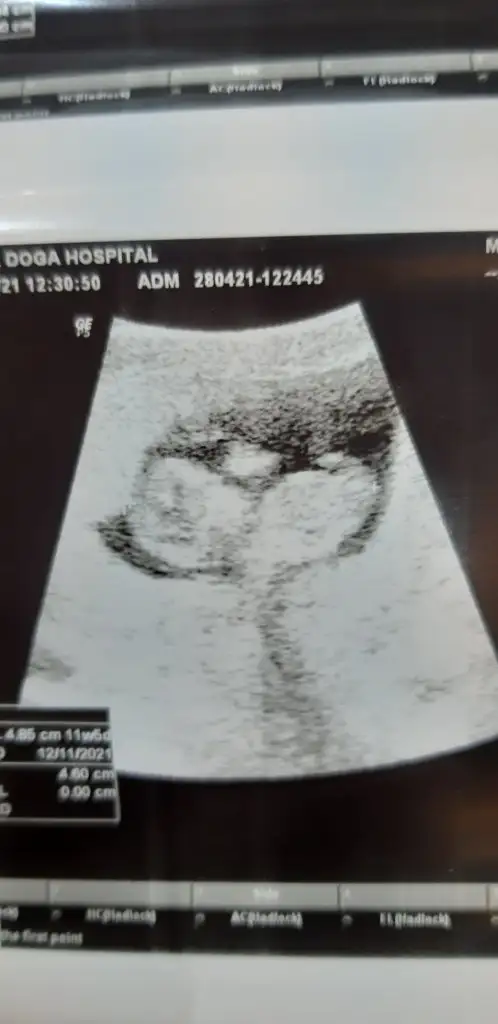

Merhaba arkadaşlar cinsiyet tahmini yapabilen var mı aramızda 🤗

11+4 görüntüleri ekliyorum . Merakla bekliyorum yorumlarimizi ..